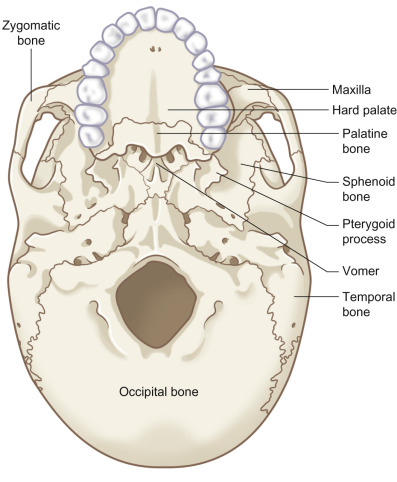

Injury to the midface can involve a complex constellation of the skeletal anatomy: the maxillary and zygomatic processes of the frontal bone, nasal bones, bones of the orbit, zygomas, ethmoids, vomer, pterygoid plates, maxilla, and palate. Both conceptually and practically, a fundamental understanding of the horizontal and vertical structural pillars of the midface skeleton is critical to understanding the diagnosis and management of these injuries. Failure to restore the structural pillars after injury can lead to inadequate projection, height, and width, resulting in a short, retruded, and widened face. The anatomical patterns if these structural pillars are compromised following the application of frontal or lateral injury forces at varied levels within the midface have been shown to be predictable, and are termed Le Fort fractures.

Surgical Anatomy

The skeletal anatomy of the cranial and midface skeleton is depicted in Figs. 1.13.4–1.13.6 .